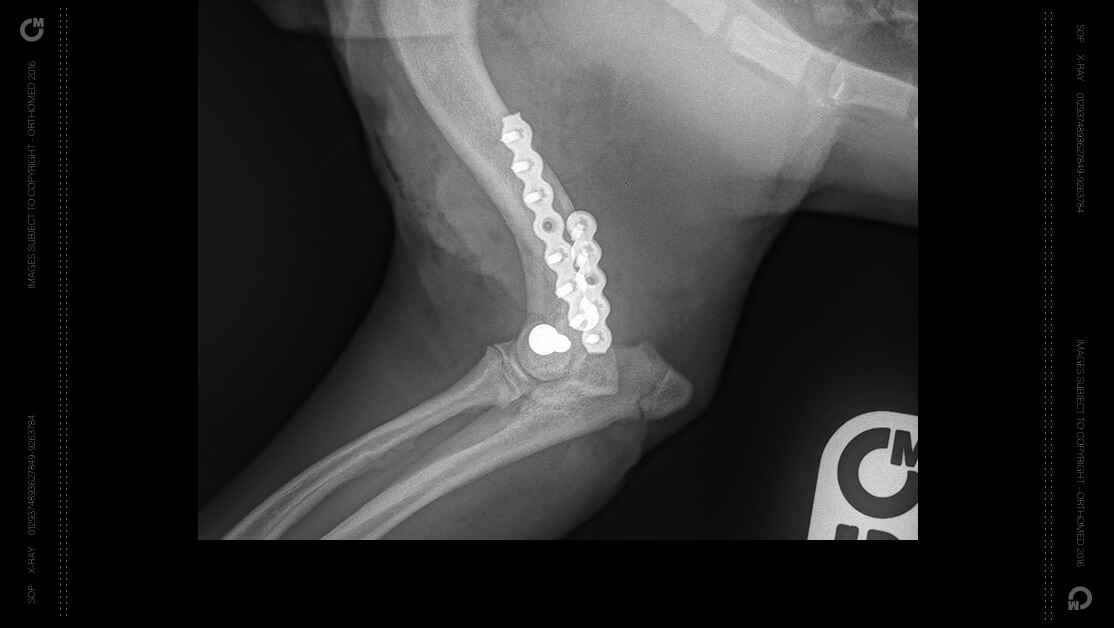

They have been applied to a wide variety fractures in canines and felines starting at 1.8kg

Small degrees of bending and twisting of the SOP™-LP is possible and no bending tees are required for this plate

The SOP LP system has been applied to a wide variety fractures in canines and felines starting at 1.8kg